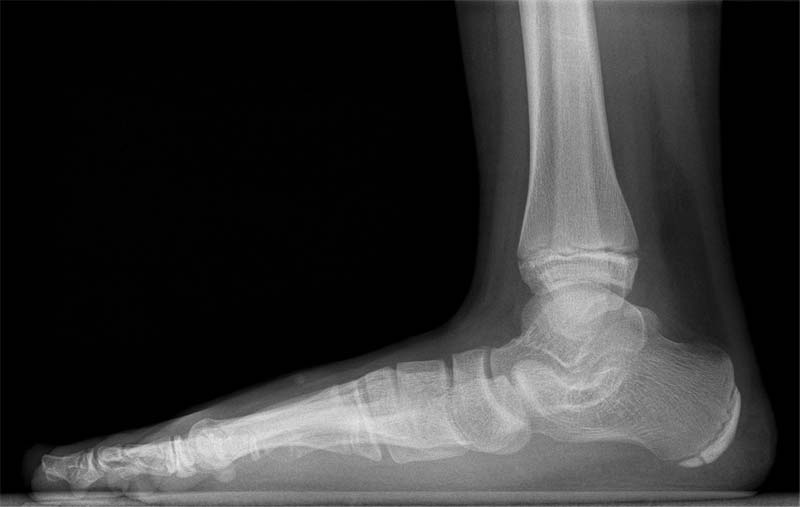

Der Plattfuß sieht häufig äußerlich aus wie der kindliche Knicksenkfuß.

Beim angeborenen Plattfuß, der eher selten vorkommt, handelt es sich um eine Fehlstellung des Sprungbeines in der Knöchelgegend. Der Plattfuß des älteren Kindes zeigt sich als Absinken des Fußlängsgewölbes mit einer Fehlstellung der Ferse.

Der Plattfuß beim älteren Kind wird durch die klinische und röntgenologische Untersuchung festgestellt. Meistens ist der Fuß ein sogenannter „flexibler Plattfuß“, das heißt die Fehlstellung korrigiert sich automatisch im Zehenspitzenstand.